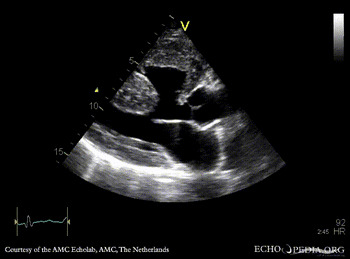

Large VSD, syndrome of Eisenmenger

AMC Echolab, AMC, The Netherlands

PLAX: Large VSD